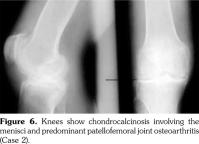

His hand X-rays showed hook like projections arising from radial aspect of second and third metacarpal heads with scapholunate advanced collapse and indentation of distal radius by the scaphoid bone. It also showed CC of the triangular fibrocartilage (Figure 6).

He had chondrocalcinosis involving the menisci and hyaline cartilage, with predominant patellofemoral joint osteoarthritis. His blood investigations to find a metabolic cause for CC were negative.